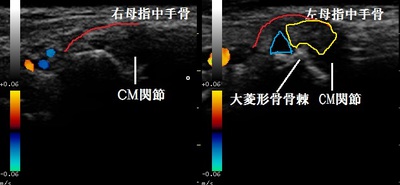

右左CM関節 超音波長軸像

当院来院時には左親指の付け根(CM関節)は腫れて熱感が著明でした。ペットボトルのふたを開けてもら

超音波検査を行ったところ、左のCM関節が右と比較して腫れていました(画像の赤線の盛り上がり)。

また関節の中には白い硬い組織が介在して(画像の黄色線)、関節液(水腫)も過剰に貯留していました

(画像の青線)。大菱形骨は骨棘が形成されていて、関節症が進行している様子も認められました。